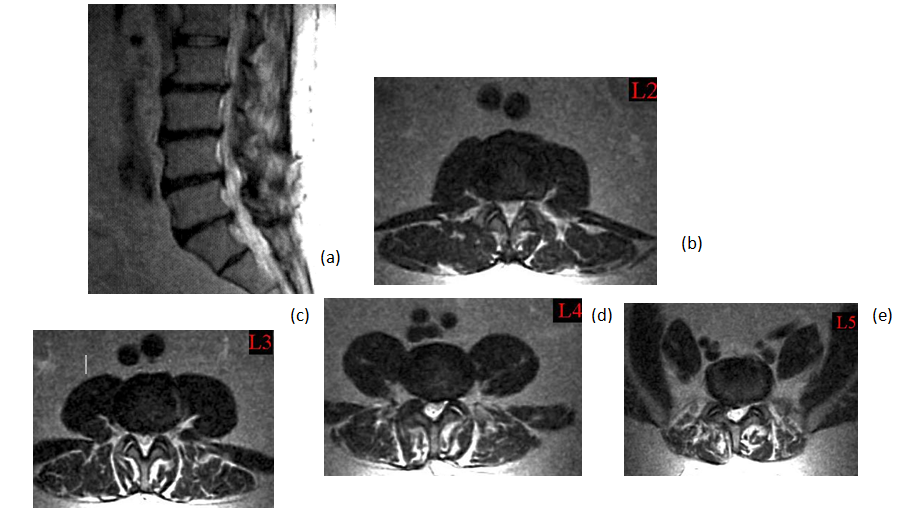

A 63-year-old patient with morbid obesity and insulin dependent diabetes mellitus suffered from spinal canal stenosis and multiple level disc protrusions at L2/3, L3/4, L4/5 and L5/S1. The largest disc was at L5/S1, > 6mm as illustrated below. His weight is 280 lbs and height 5’ 8” (Figure 4–16). The patient complained of back pain and radicular symptoms including the anterior and surface of both thighs and legs, and back of the foot with more severe pain on the right side associated with some neurogenic claudication. Previously the patient refused open surgery with fusion, because of increased risk in morbid obese and diabetic patients and requiring a multi level extensive open spinal fusion. After reviewing his MRI scans, (Figure 4) minimally invasive endoscopic microdecompression surgery was recommended to the patient as a solution for his spinal condition. He agreed to proceed with MISS surgery. It can be very time consuming to reach the foramen in obese patients since the fat distribution gives a false orientation of the actual location of the spine in relation to the skin surface. By using the GPS system to triangulate the 3D orientation of the foramen under fluoroscopy, the height, width and depth of the soft tissue in relation to the foramen was determined the microdecompression was successfully performed. Bilateral L2-L5 endoscopic microdecompressive discectomy (Figure 5–16) was performed in the lateral decubitus position on two sittings of less than 1 hour for each side to avoid a prolonged single procedure. The patient reported marked relief of his back symptoms and lower limb numbness on the next post operative day with a better range of motion and ambulation.

Figure 4 (a) Sagital T2 view MRI showing multi-level disc protrusions and canal stenosis (b, c, d, e) with bilateral nerve roots compression.